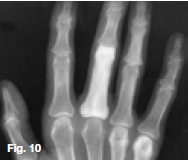

Figures 1, 2, & 3 show a mixed radiolucent/opaque lesion affecting the maxilla, crossing the midline in an edentulous patient, causing flattening of the palate. A lateral skull radiograph of another patient (Fig. 4) shows osteoporosis imperfecta in the posterior and anterior parts of the skull (green arrows) along with thickening of the calvarium and cranial vault which are cardinal radiological signs of the condition. Figures 5 & 6 illustrate "cotton wool" radio-opacities in the skull and the base of the skull shows dense sclerosis. All the images mentioned so far are typical features of Paget's disease. Sir James Paget, surgeon and pathologist who is best remembered for naming Paget's disease. The disease is idiopathic and can be divided into three stages: initial bone resorptive phase, vascular phase with osteoblastic repair, and approximal/ sclerosing phase. The jaws are involved in approximately one in Ave cases, with the maxilla being affected about twice as frequently as the mandible. During the initial phase of bone resorption, the affected bones may be deformed or painful, particularly the weight-bearing structures such as the long bones of the legs (Fig. 7A & B). Later the affected bones expand, commonly in the maxilla, mandible or cranium. At this stage, the dental patient who wears full dentures may complain that the fit of the dentures is becoming progressively poorer. When the maxilla is affected, the alveolar ridge widens and the palatal vault can flatten (Fig. 2). When teeth are present, they may become increasingly spaced, with extensive jaw enlargement. Neurologic complaints can result from increased deposition of bone in the areas of the foramina of the skull causing headaches, auditory disorders progressing to deafness, visual disorders progressing to blindness, facial paresis, and vertigo. The bones are relatively brittle; hence, fractures are likely. Generalised radiolucency/osteoporosis intermediate stage with mixed radiolucency/radiopacity, "driven snow" coarse trabeculation, "cotton wool" radio-opacities in the final stage (Figs. 5 & 6). Hypercementosis, loss of lamina dura, obliteration of the periodontal ligament spaces (Fig. 8) and external root resorption (Fig. 9) may also be present. The upper hand wrist radiograph (Fig.10) of another patient shows the disease affecting the phalanx of the third digit.